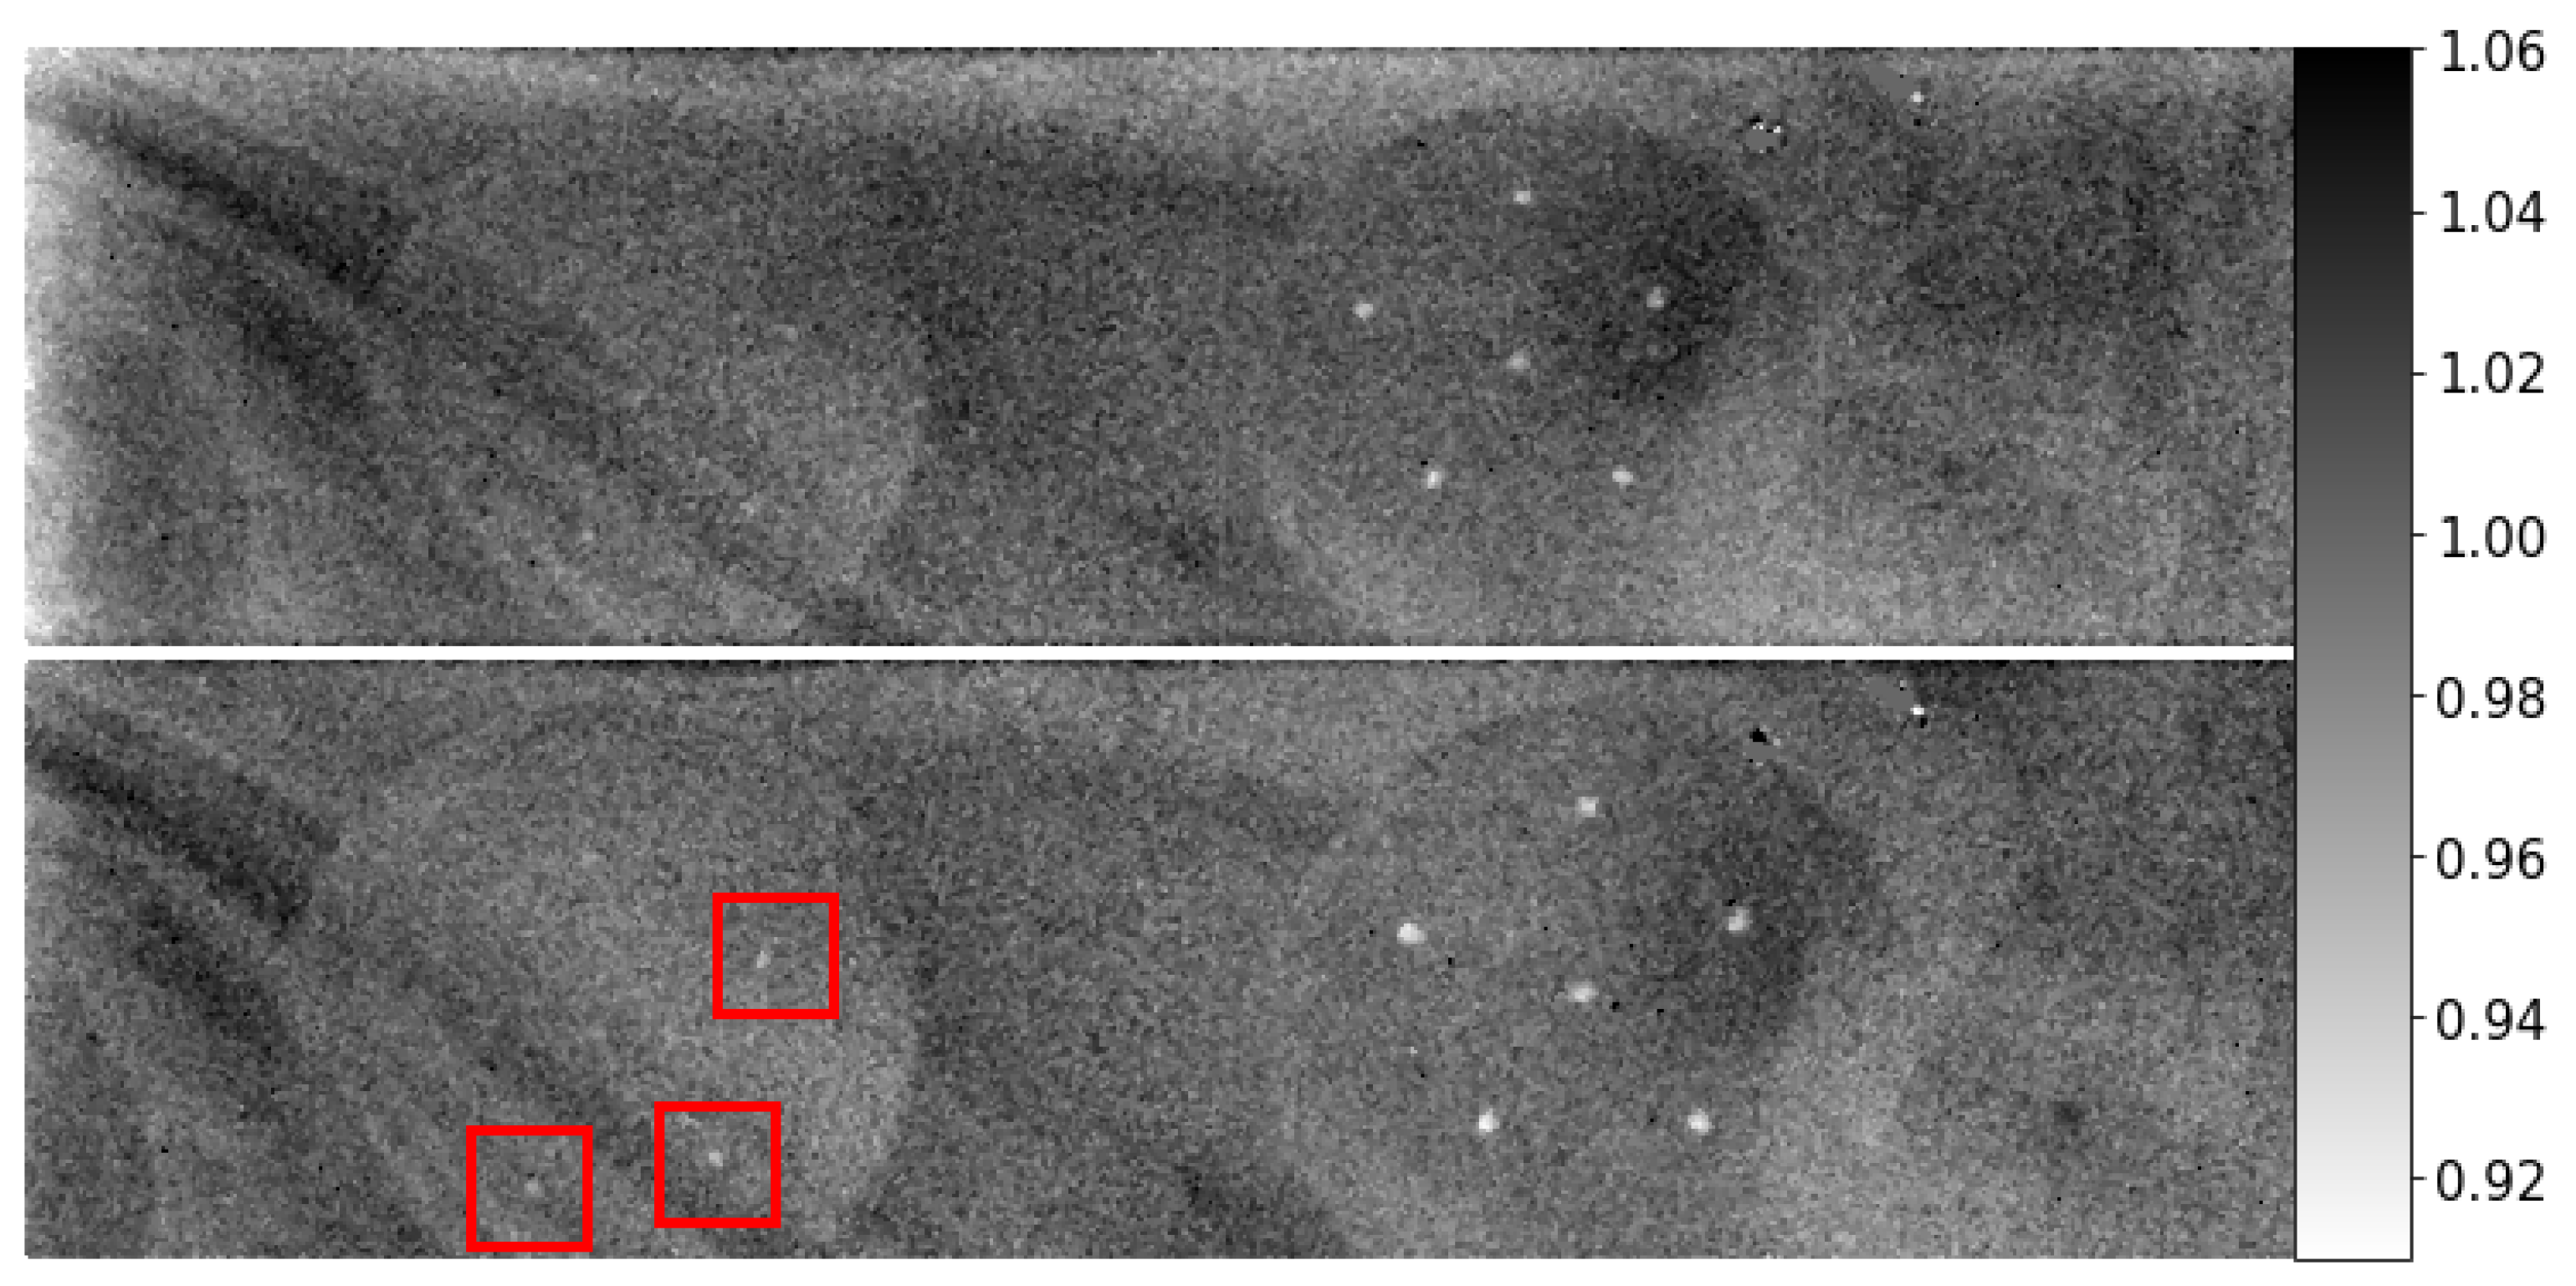

3.1. Energy-Integrated SPR

3.2. Energy-Resolved SPR